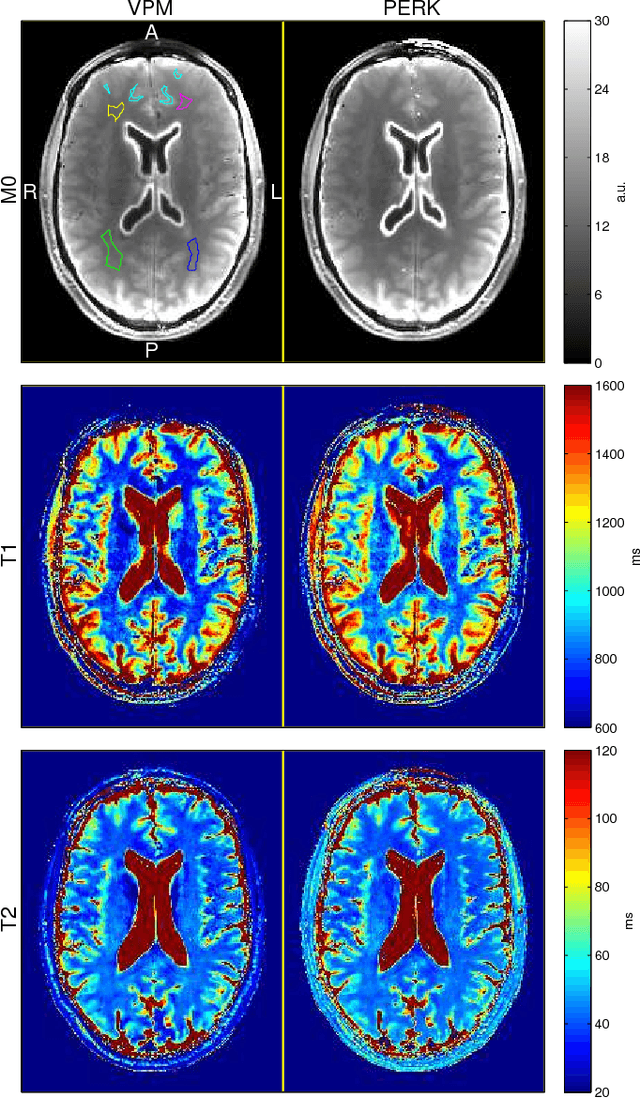

This paper introduces a fast, general method for dictionary-free parameter estimation in quantitative magnetic resonance imaging (QMRI) via regression with kernels (PERK). PERK first uses prior distributions and the nonlinear MR signal model to simulate many parameter-measurement pairs. Inspired by machine learning, PERK then takes these parameter-measurement pairs as labeled training points and learns from them a nonlinear regression function using kernel functions and convex optimization. PERK admits a simple implementation as per-voxel nonlinear lifting of MRI measurements followed by linear minimum mean-squared error regression. We demonstrate PERK for $T_1,T_2$ estimation, a well-studied application where it is simple to compare PERK estimates against dictionary-based grid search estimates. Numerical simulations as well as single-slice phantom and in vivo experiments demonstrate that PERK and grid search produce comparable $T_1,T_2$ estimates in white and gray matter, but PERK is consistently at least $23\times$ faster. This acceleration factor will increase by several orders of magnitude for full-volume QMRI estimation problems involving more latent parameters per voxel.